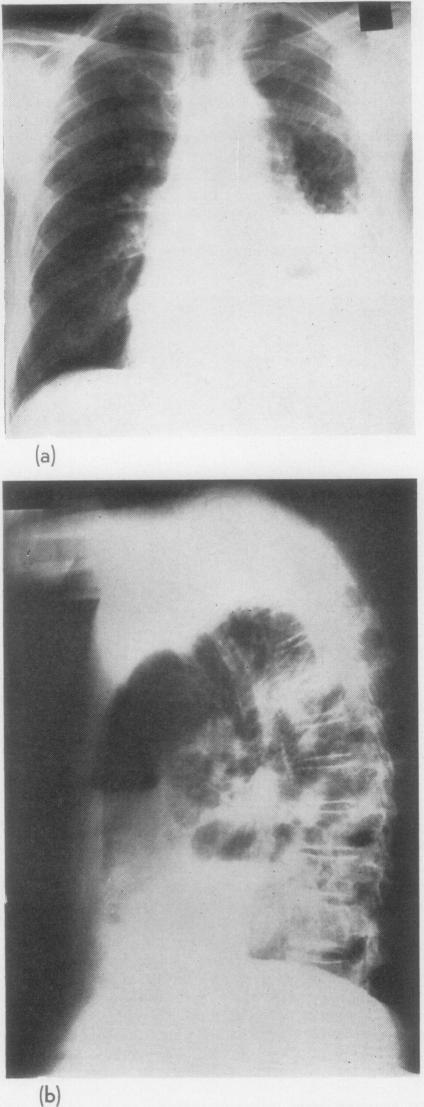

GINGELL J C

Thorax. 1965 May;20(3):261-9. doi: 10.1136/thx.20.3.261.